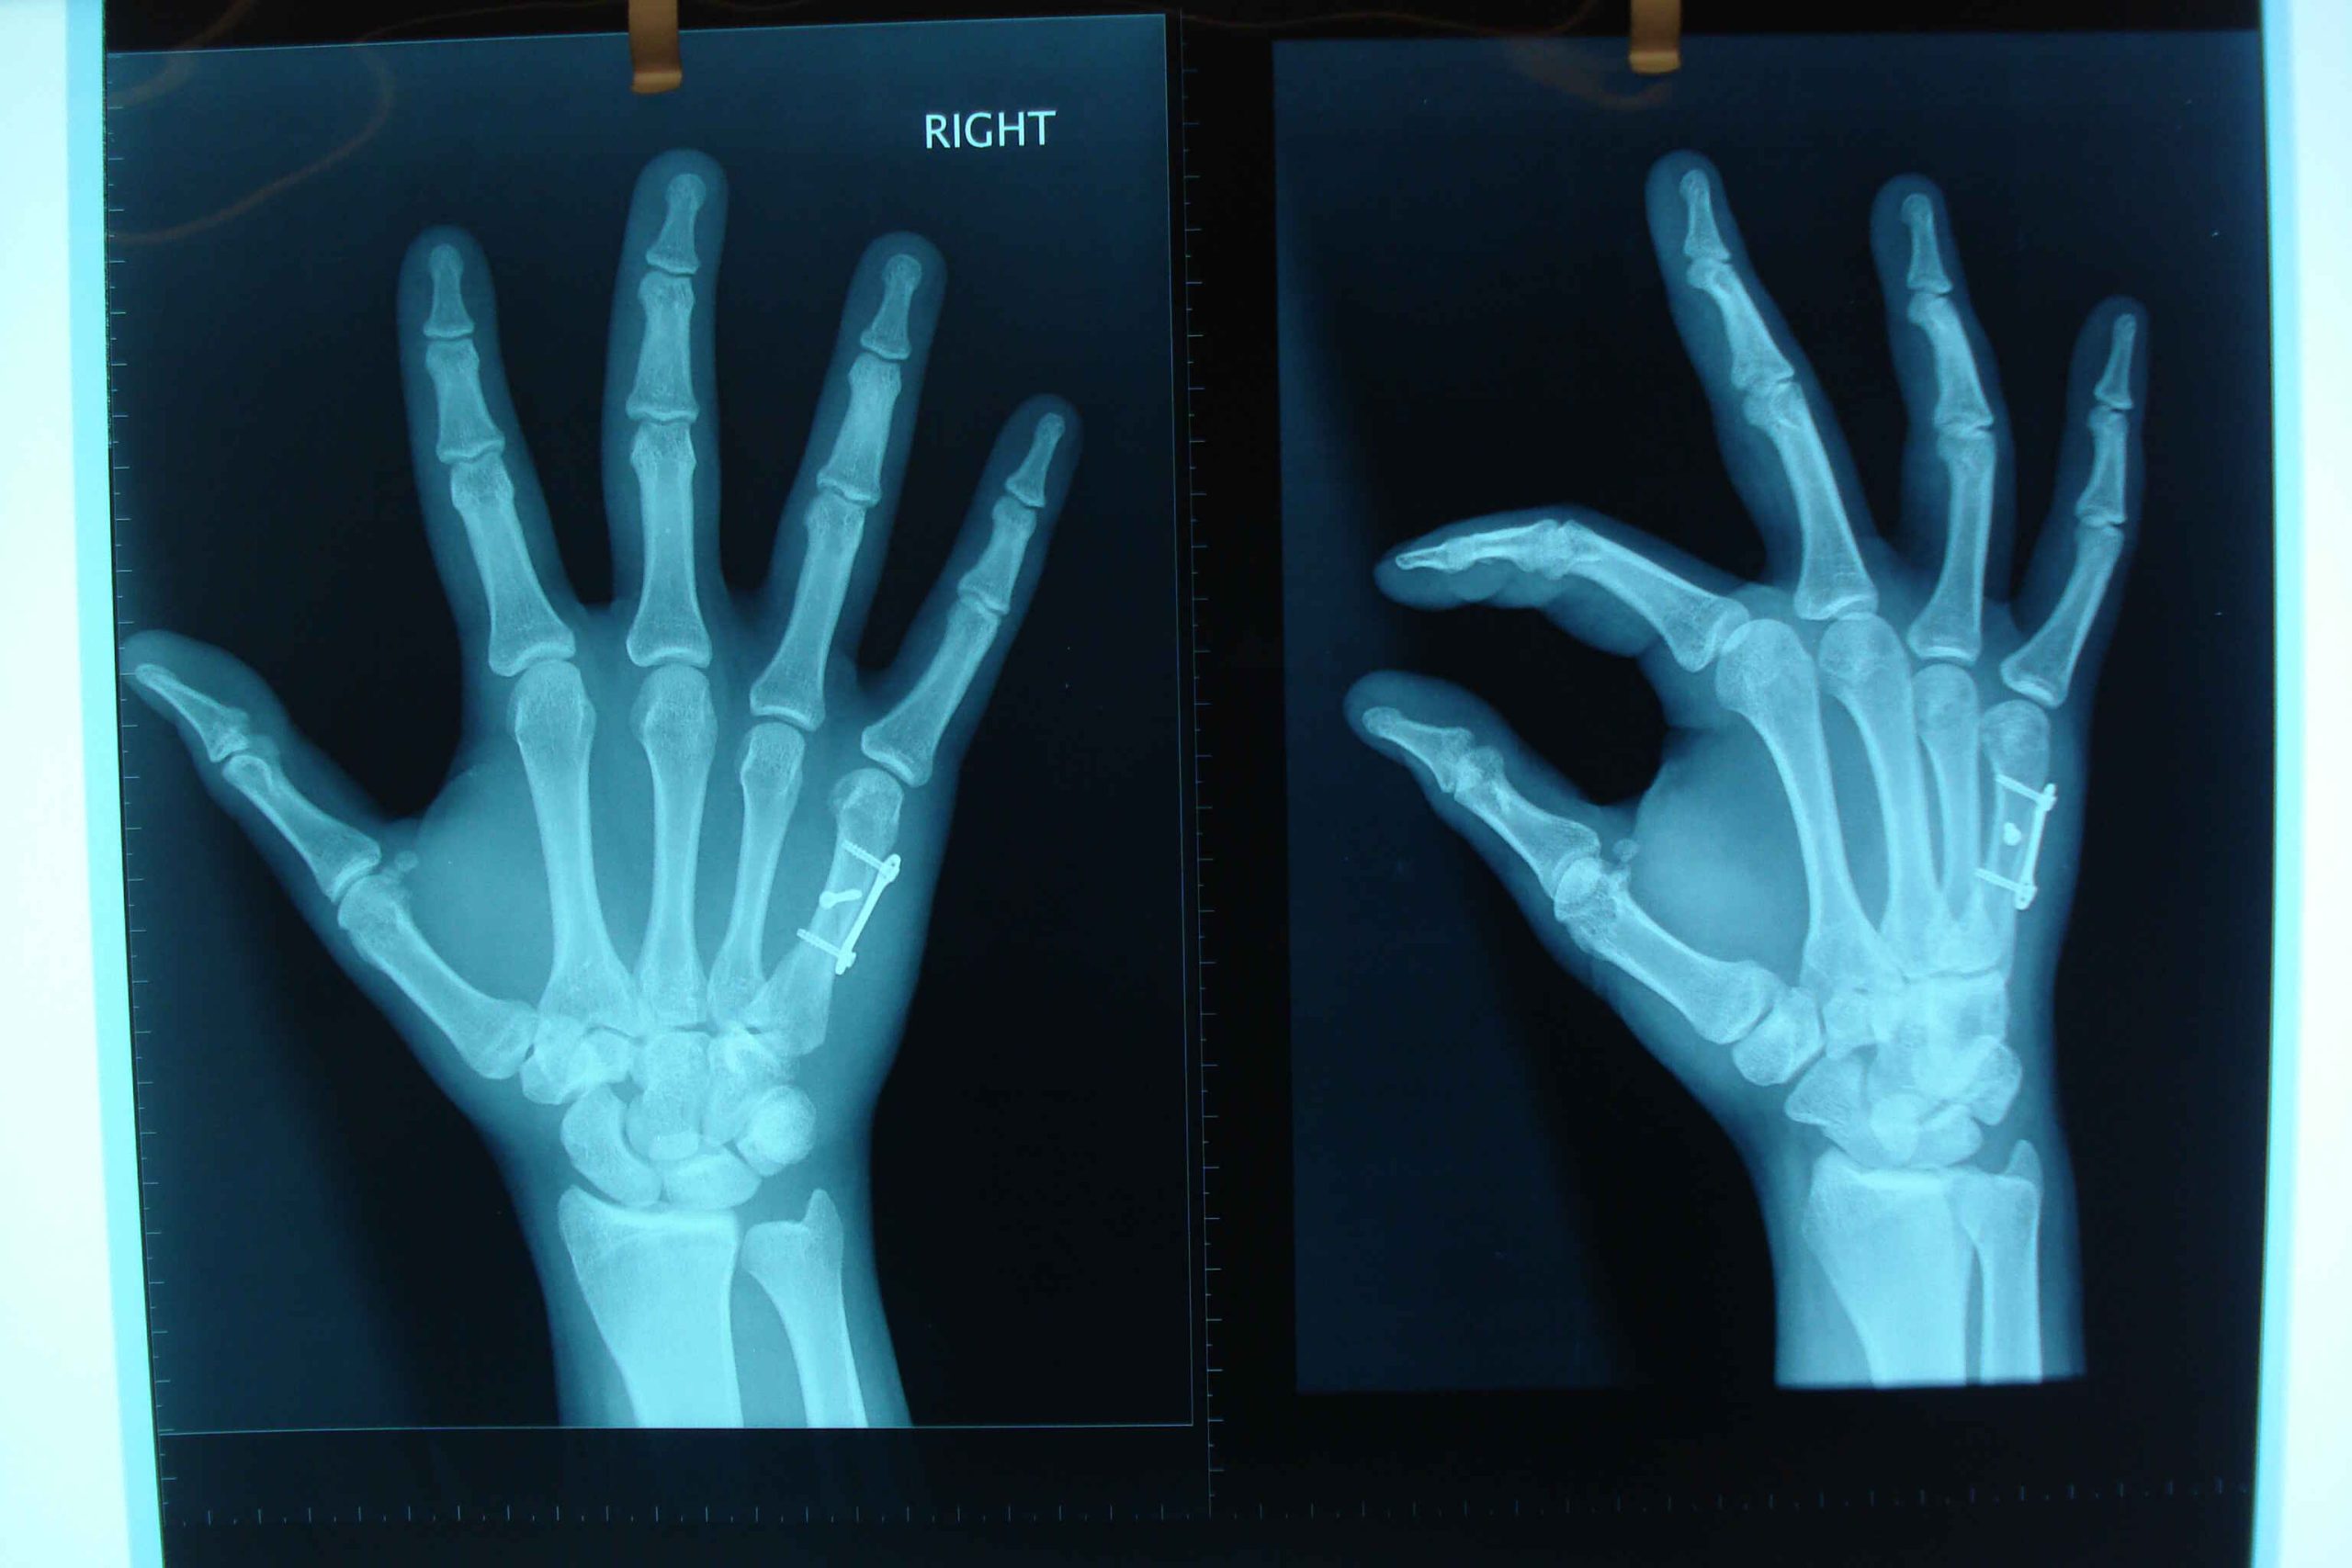

Η φυσιολογική σωματική δραστηριότητα, ακόμα και το περπάτημα, θα μπορούσε να σχετιστεί με μειωμένο κίνδυνο κατάγματος στις μεταεμμηνοπαυσιακές γυναίκες. Σε αυτό το συμπέρασμα κατέληξε έρευνα που δημοσιεύθηκε του Πανεπιστημίου του Μπάφαλο που δημοσιεύθηκε στο JAMA Network Open. H μελέτη αποτελεί την πιο συνολική αξιολόγηση σωματικής δραστηριότητας και καταγμάτων στις γυναίκες μεγαλύτερης ηλικίας.

Στην έρευνα μελετήθηκαν περισσότερες από 77.000 γυναίκες που παρακολουθήθηκαν για περισσότερα από 14 χρόνια. Κατά τη διάρκεια της περιόδου παρακολούθησης το 33% των συμμετεχουσών ανέφερε ότι υπέστη τουλάχιστον ένα κάταγμα.

Οι γυναίκες που είχαν περισσότερη σωματική δραστηριότητα είχαν 18% χαμηλότερο κίνδυνο κατάγματος ισχίου και 6% χαμηλότερο κίνδυνο καταγμάτων γενικά.

«Το κάταγμα είναι κάτι αρκετά κοινό στις μεταεμμηνοπαυσιακές γυναίκες και σχετίζεται με την απώλεια ανεξαρτησίας, κινητικούς περιορισμούς και αυξημένη θνησιμότητα», εξήγησε η Δρ. Wactawski-Wende.